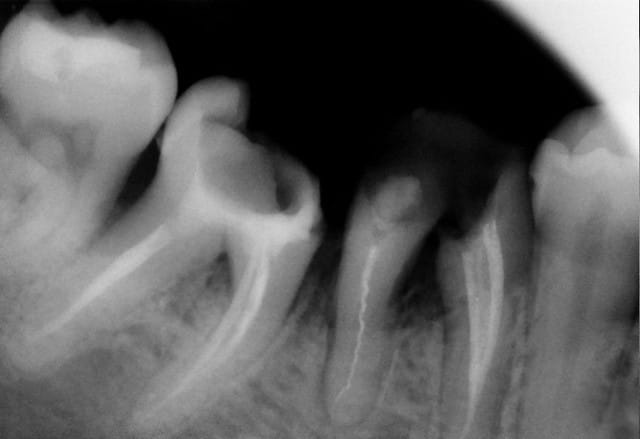

Tu espères vraiment faire quelque chose de la racine qu'on voit sur la dernière photo ?

teethsurfer, je comprends mal ton intervention et ce que tu en attends.

Entre ton désir compréhensible de prolonger une situation qui ne posait pas problème sur une personne sur la fin de sa vie et la cruelle évidence d'une dent qui mérite l'extraction, j'ai bien peur que tu te fourvoies.

J'ai déjà récupéré de nombreuses racines à ce stade et les ai utilisées comme piliers de bridges ou les ai couronnées, dans la mesure ou l'ancrage alvéolaire était solide et en respectant les furcations pour y assurer l'hygiène.

La gencive lasérisée devient très ferme avec le temps et le déchaussement se stabilise. Ces restaurations se comportent bien sur un recul de plusieurs années.

Un exemple: une 46 avec furcation linguale dénudée après lasérisation et restauration par une endocouronne céromère réalisée il y a 9 ans et sans signe clinique avec une excellente attache gingivale malgré la perte osseuse, les 3 avant dernières images ont été prises lors d'un contrôle en mars dernier ...

9 années pour cette patiente de 90 ans, cela vaut bien le coup d'essayer vous ne croyez-pas? (dernière radio)

Avec le laser, on devient bien plus conservateur...